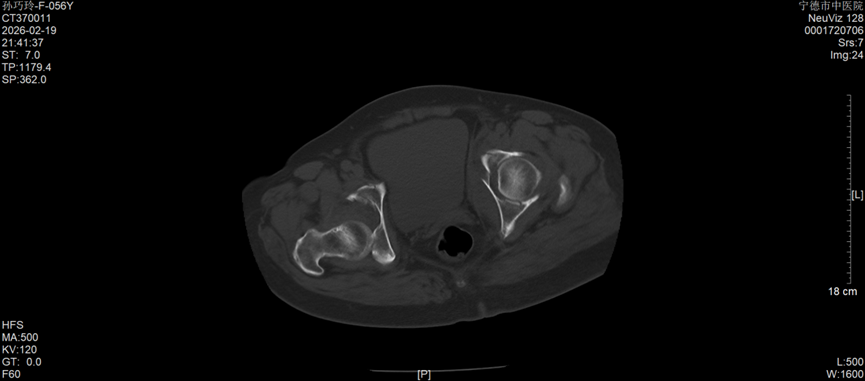

今年57岁的孙女士,因车祸外伤被紧急送往宁德市中医院创伤骨科就诊,经检查确诊为右侧髋臼后壁骨折伴股骨头后脱位,左侧髋臼T形骨折且累及四边体。据了解,髋臼骨折多由高能量损伤引发,其解剖结构复杂,毗邻重要血管神经,复位精度要求高、手术风险大,一直是创伤骨科领域的高难度手术,而双侧髋臼骨折更是该领域中极具挑战性的病例,不仅创伤重、术中出血风险高,诊疗难度也大幅提升。更为棘手的是,孙女士还合并有严重糖尿病及Ⅰ型呼吸衰竭,这无疑进一步增加了病情的复杂性和诊疗的艰巨性。